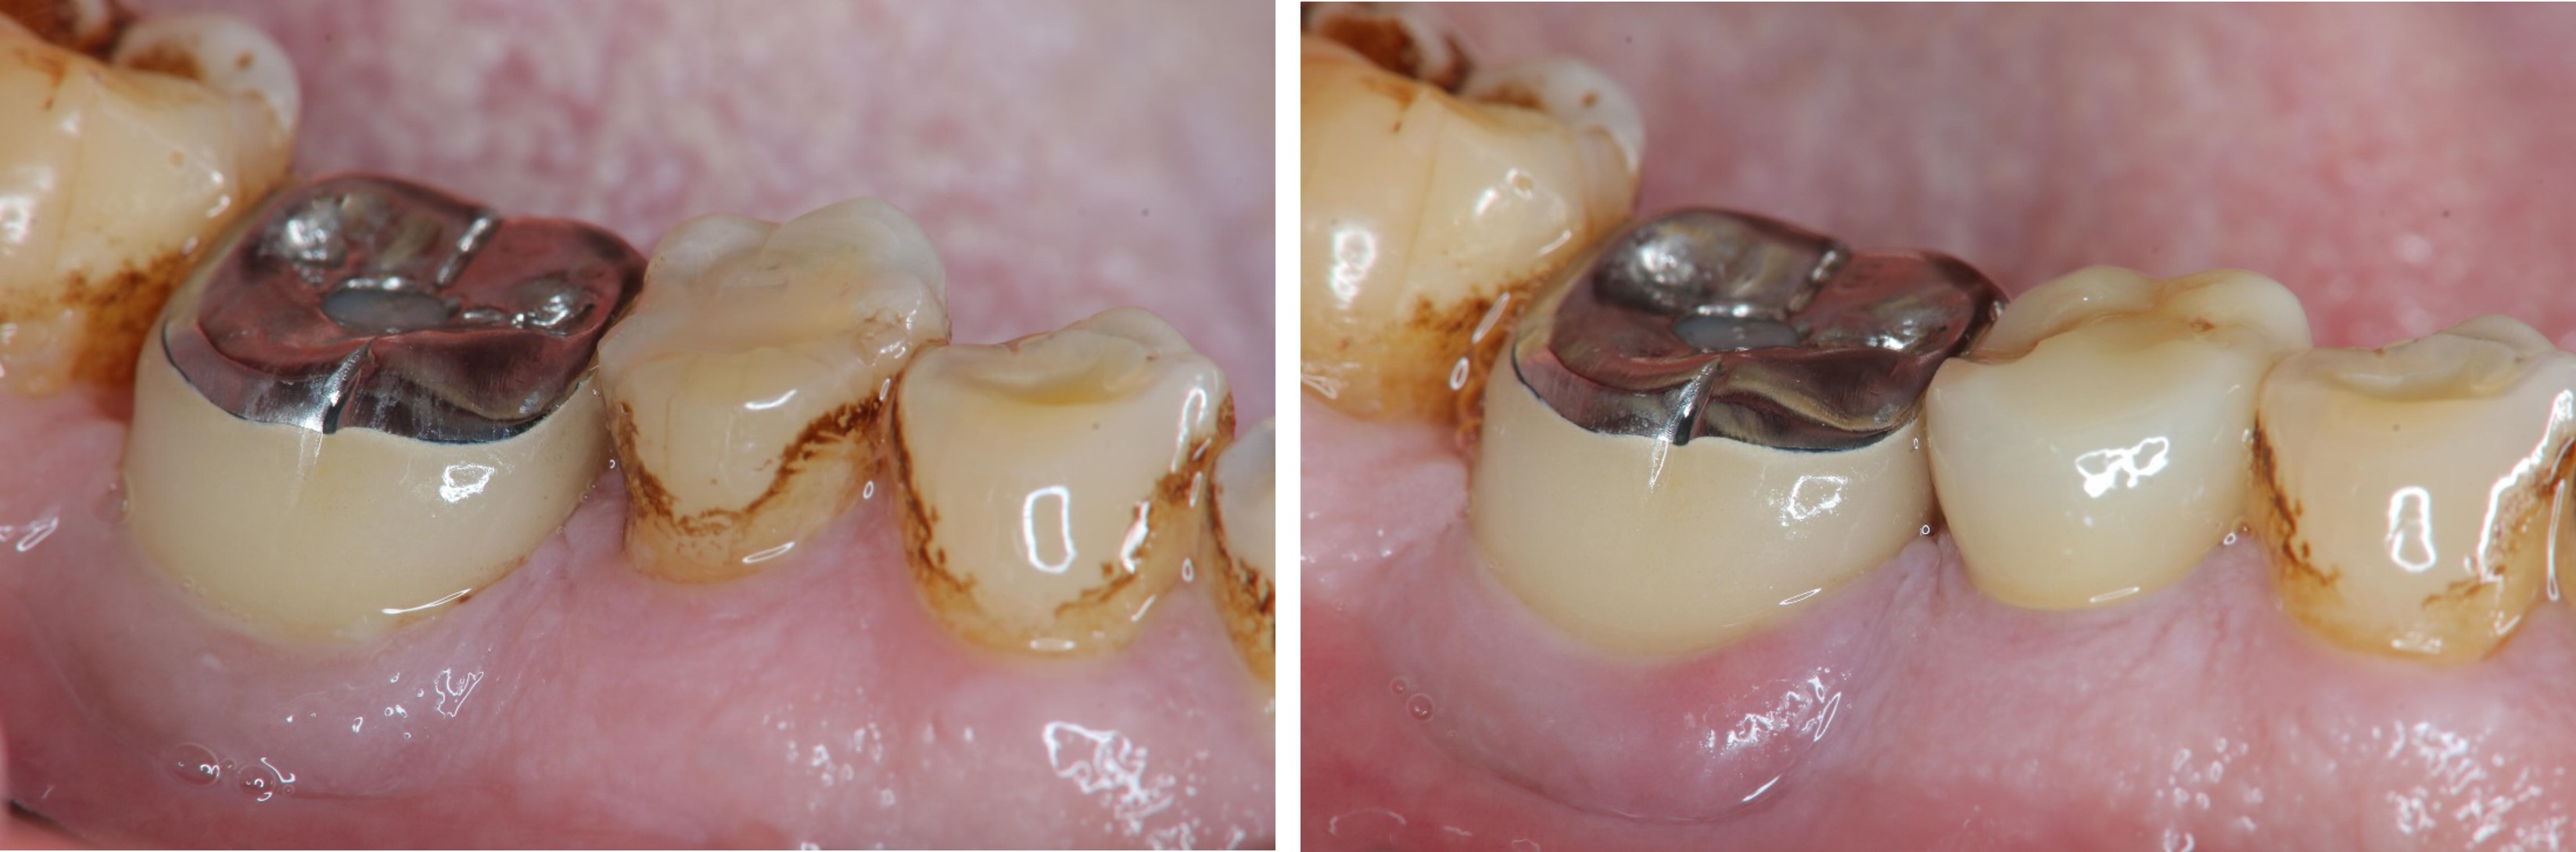

治療後口內照

患者的咀嚼機能逐漸恢復正常

術前、術後比較

幾年下來,這一類連續的治療,長期的癒後相當穩定,因此對於有心保留牙齒的患者,提供了另一個方法,是植牙之外的另一個重要的治療方式。